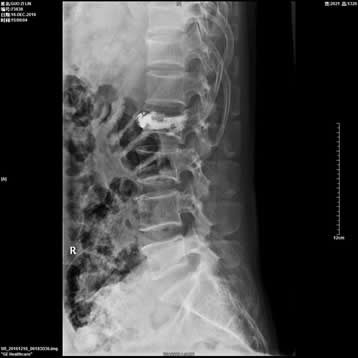

2、开展了椎体压缩性骨折的微创椎体成形(PKP)手术。

3、开展了椎间孔镜微创治疗腰椎间盘突出症手术。

4、腰椎间盘摘除椎间融合器椎体融合(cage)手术。

5、颈腰椎间盘突出臭氧射频消融手术。